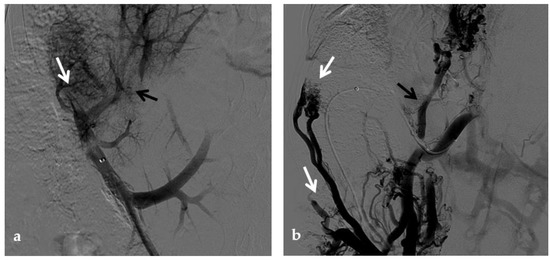

Figure 11.

Anteroposterior view of a percutaneous transmesenteric portography imaging series of an acute complete portal vein thrombosis occurred early after pediatric split-liver transplantation in a 1-year-old female with biliary atresia. (a) Superior mesenteric portography performed through a surgically-placed transmesenteric sheath (white arrow) shows total occlusion of the main portal vein and its intrahepatic branches, with opacification of several portosystemic varices (black arrows). (b) Superior mesenteric portography shows effective embolization of the portosystemic shunts to reduce the flow-steal phenomenon. A mixture of N-butyl cyanoacrylate and iodized oil and metallic microcoils (arrows) were used. (c) Portography image shows angioplasty with a 5-mm non-compliant balloon catheter performed on a stiff guidewire advanced through the common portal vein (white arrow). Note the spontaneous remaining opacification caused by the mixture of N-butyl cyanoacrylate and iodized oil (black arrows). (d) Final superior mesenteric portography shows restored opacification of the portal vein anastomosis, the umbilical recess of the portal vein (black arrow) and the intrahepatic segment 2 and segment 3 branches (white arrows), with no contrast filling of the portosystemic shunts.

A transmesenteric approach can be used both in early PVT and in chronic PVT when transhepatic and/or transsplenic access fails. Kim et al. and Cheng et al. described the use of the transmesenteric access for portal vein revascularization and stent placement for PVT during transplantation and early PVT [83,84]. Cavalcante et al. showed that PV revascularization using a transmesenteric approach may be an alternative procedure to reestablish the portal flow to the liver graft in selected cases, being a therapeutic addition to other treatment strategies currently used to treat chronic PVT. It has acceptable technical and clinical success rates, long-term patency, and a low rate of procedure-related complications [25] (Figure 11).